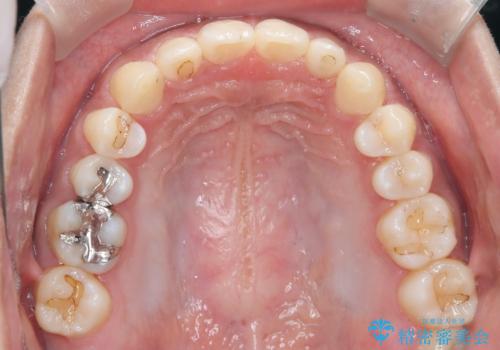

【インビザライン】空隙歯列の矯正

- 前歯の隙間を主訴に来院されました。

なるべく目立たない治療を希望されましたので、インビザラインにて治療を行なっております。

単純に前歯の隙間の閉鎖をしてしまうと、前歯に早期接触が生まれ、臼歯が噛まなくなってしまいます。適切な治療計画を立てることで、噛み合わせも良好な結果を得ることができました。